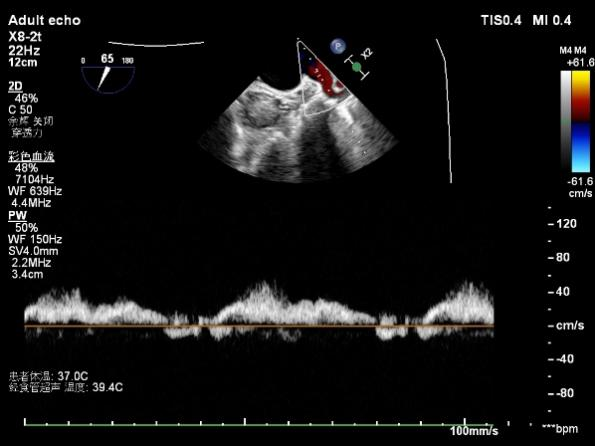

与患者及家属充分沟通并征得同意后,手术如期举行。术中在食道超声引导下,王正忠团队凭借精湛的介入操作技术,从下腔静脉右房到左房穿刺房间隔,手术先后下了3个二尖瓣夹合装置,精准夹合重度脱垂反流的二尖瓣,手术效果立竿见影,食道超声显示夹合组织充分,二尖瓣反流量由重度(4+)降至微量(1+)。术后随访患者恢复良好,心功能得到明显改善。

△TEER术后二尖瓣反流由重度变成少量